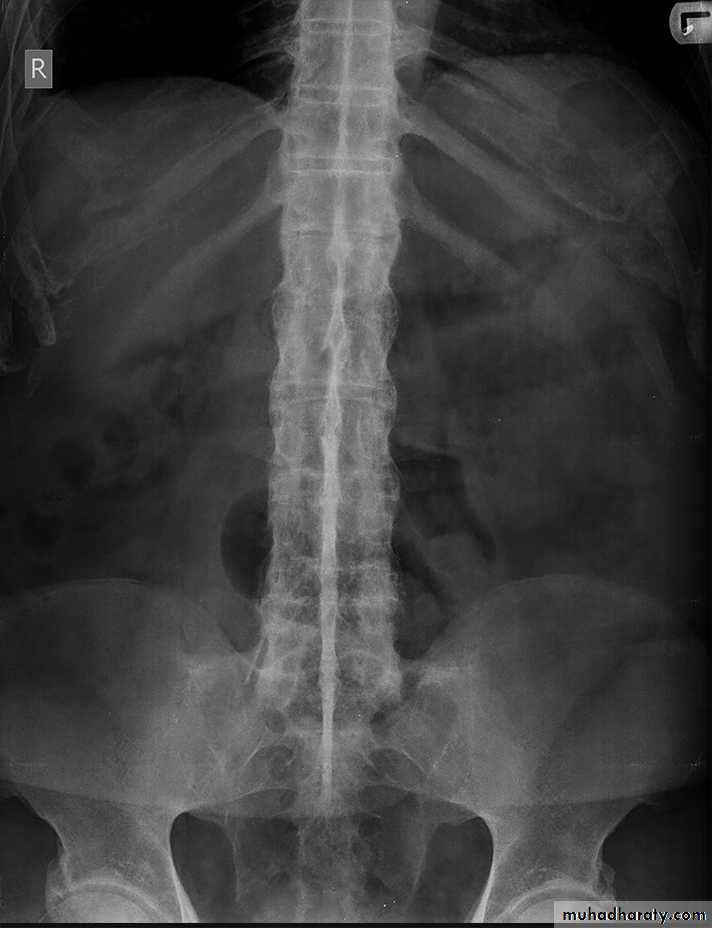

Lumbar spondylosis. There is distal narrowing and a vacuum

phenomenon is present in the degenerative discs. Marginal osteophytes arepresent. Inferiorly the facet joints show features of degeneration and, with the increase in lordosis, the spinous processes are in contact